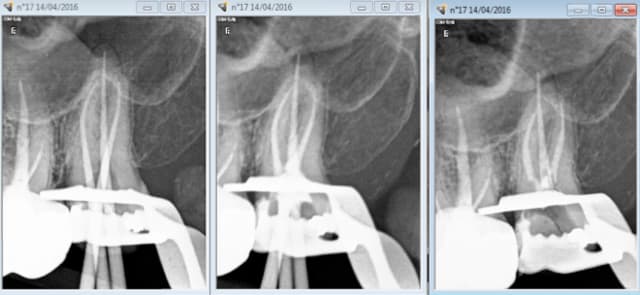

14/04/2016 à 17h25

vu le tarif de merde des endos tu peux aussi t'arreter au cone scellé. -)

Ca donne de très belles images. tout comme l'essayage du cone d'ailleurs, on a pas forcément mieux condensé. -)-)

Capture d e cran 2016 04 14 15.23 - Eugenol

Capture d e cran 2016 04 14 15.25 - Eugenol